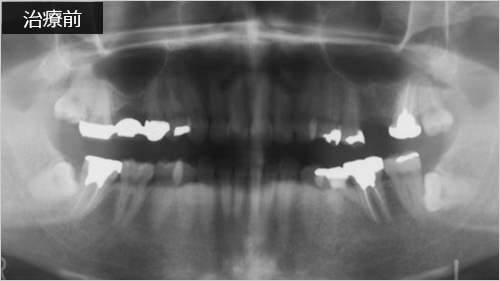

インプラント症例7

45歳 男性- 治療期間 4か月(埋入手術から上部構造装着まで)

- 治療費 ¥1000,000(税別)

右側(Rと書いてあるほう)をご覧ください。骨に入っている部分と骨から出ている部分の長さの比に注目です。骨が少なくてもインプラント可能です。術後6年が経ち順調な経過といえます。